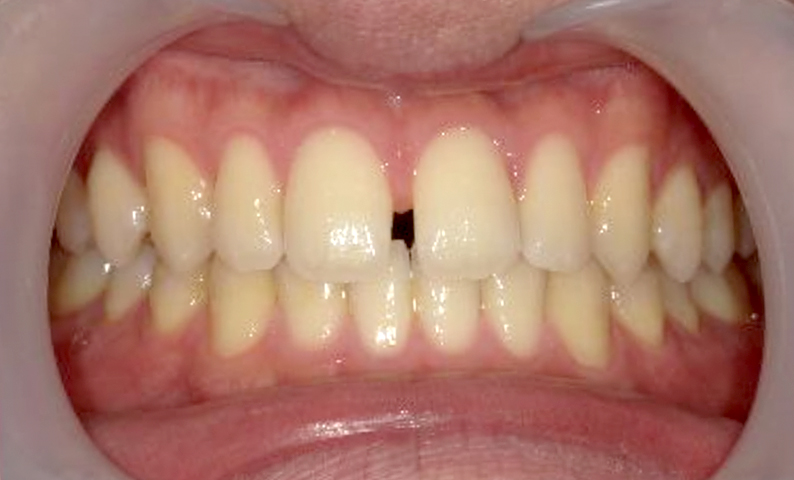

| 治療前 | 治療後 |

|---|---|

|